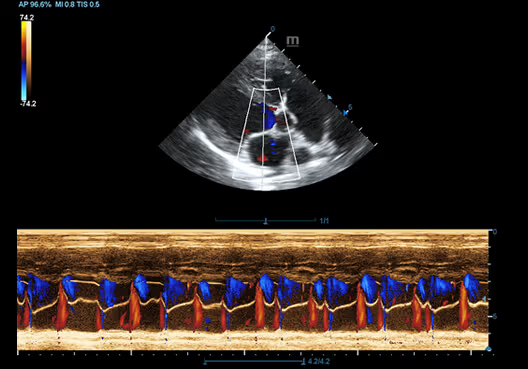

Color M-Mode, Kalp, Köpek

Color M-Mode, Kalp, Köpek